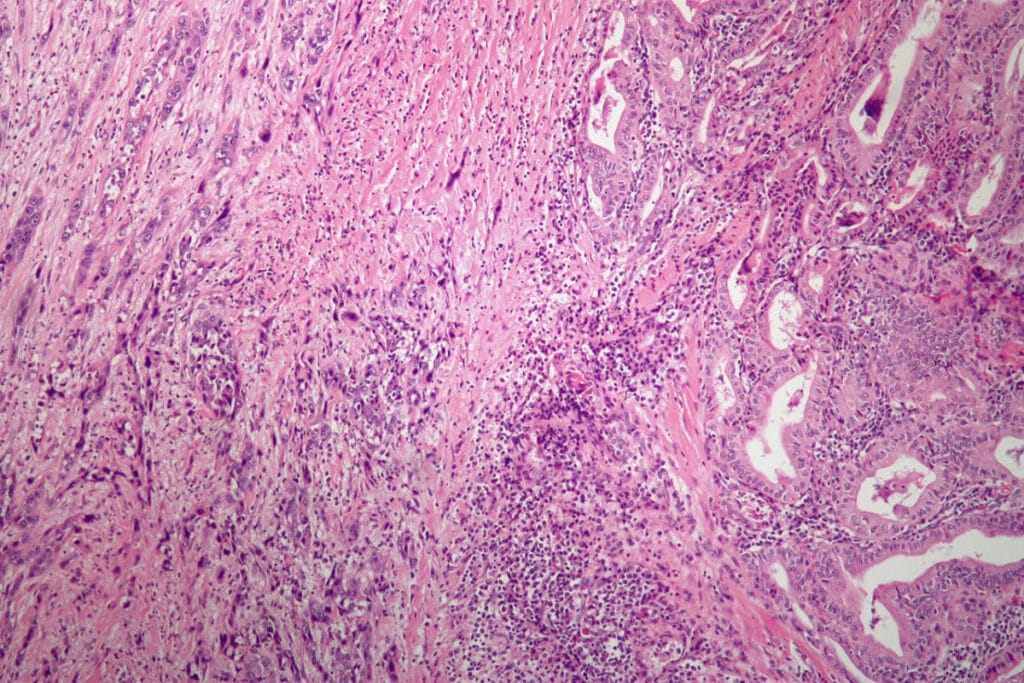

역형성암 (Anaplastic Thyroid Carcinoma)

역형성암은 갑상선암 중 가장 드물지만 가장 치명적인 형태로, 매우 빠른 성장 속도와 강한 침습성을 보입니다. 주로 고령에서 발생하며, 진단 시 이미 국소 침습 또는 원격 전이가 흔하게 발생합니다. 대부분 수술이 어렵고 항암화학요법과 방사선 치료를 병합하지만, 평균 생존 기간이 매우 짧습니다.

병리학적 특징

🟦 고도로 미분화된 세포, 광범위한 괴사

세포 형태가 다양하고 비정형적이며, 조직 내 괴사가 흔하게 나타납니다.

By Nephron – Own work, CC BY-SA 3.0, https://commons.wikimedia.org/w/index.php?curid=8298744